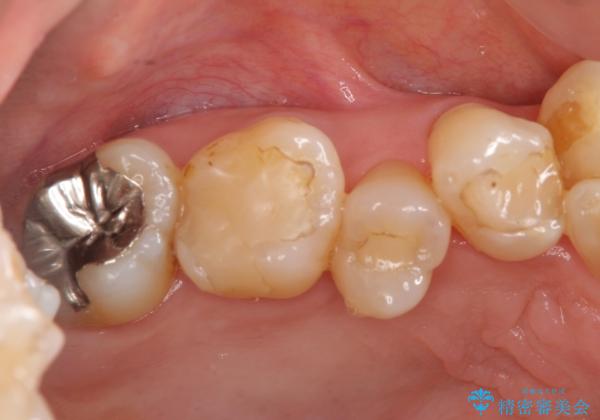

- 奥歯の詰め物のやり替えを希望して来院。

銀歯と、プラスチックをセラミックにかえました。

古い詰め物を取るときに、しっかり虫歯はとっています。

- 合計 19.8万円 右上7:セラミックインレー 7万円、右上6:ジルコニアクラウン10万円、仮歯1万円費用は治療当時の料金となります

右上6番は詰め物が大きく、インレーではなくクラウンとしました。